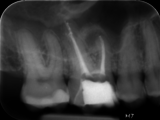

Impressionen zur Offenen Sprechstunde Endodontie (Quelle: Bildarchiv Akademie Karlsruhe)

Zur BildergalerieOffene Sprechstunde Endodontie